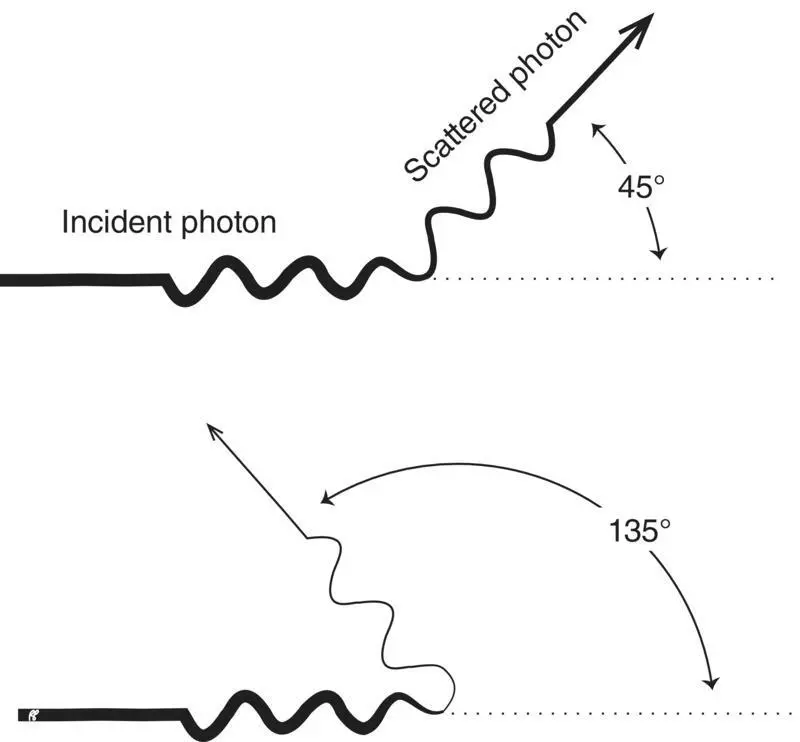

Figure 2.4 Photoelectric effect.

Charged particles (alphas, betas, and positrons) interact with the electrons surrounding the atom’s nucleus by transferring some of their kinetic energy to the electrons. The energy transferred from a low‐energy particle is often only sufficient to bump an electron from an inner to an outer shell of the atom. This process is called excitation. Following excitation, the displaced electron promptly returns to the lower‐energy shell, releasing its recently acquired energy as an X‐ray in a process called de‐excitation ( Figure 2.8). Because the acquired energy is equal to the difference in binding energies of the electron shells and the binding energies of the electron shells are determined by the atomic structure of the element, the X‐ray is referred to as a characteristic X‐ray.